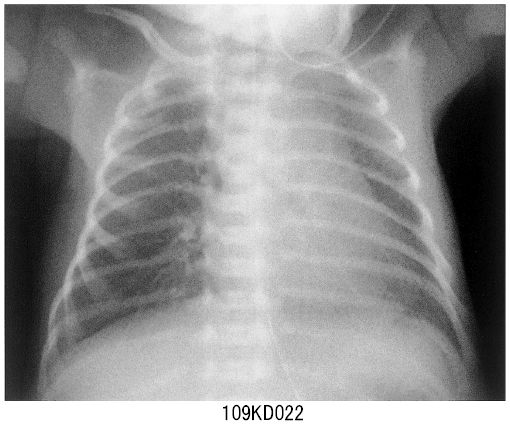

【期間限定!最安値挑戦】 症例に学ぶ新生児X線診断 語学+参考書の詳細情報

症例に学ぶ新生児X線診断。新版胸部単純X線診断: 画像の成り立ちと読影の進め方 | 林 邦昭。目でみる症例 ニューモシスチス肺炎 (臨床雑誌内科 95巻4号。

症例に学ぶ新生児X線診断

症例に学ぶ新生児X線診断